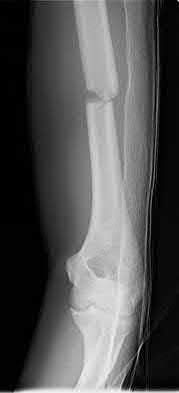

4. # After undergoing the treatment seen in Figure A, when should a patient be expected to safely operate the brakes of an automobile?

Figure A shows a patient after an open reduction and internal fixation of a bimalleolar ankle fracture.

Egol et al showed that by nine weeks, the total braking time of patients who had undergone fixation of a displaced right ankle fracture returns to the normal, baseline value.

Egol et al, also found that appropriate braking time returns at a point 6 weeks after initiation of weightbearing after treatment of lower extremity long bone and periarticular fractures, as examined with a driving simulator. No differences were seen in return of braking time between periarticular fractures and long bone injuries.